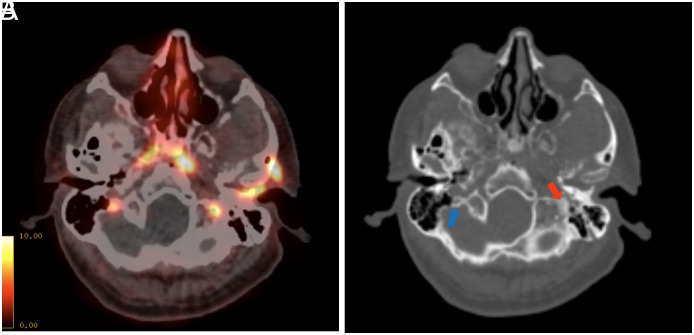

Results: All patients with a skull metastasis showed multiple other metastatic bone lesions, and 6 (33.3%) had visceral metastasis. Seven (38.9%) patients had solitary skull lesions, whereas 11 (61.1%) had multiple skull metastases. Twenty-two out of 37 (59.5%) metastatic lesions had no CT counterpart. The median SUVmax was significantly higher in metastatic lesions with a CT counterpart (median 9.09 vs. 4.63, P = .018). At a median follow-up of 23.4 mo (interquartile range [IQR] 8.7-34.1) after detection of skull metastasis, 5 out of 11 (45.5%) hormone-sensitive and all castration-resistant patients died of PCa. The median survival of patients with castration-resistant disease was 9.92 months.

Conclusion: The majority of PSMA-detected skull metastases did not show a CT counterpart, which may explain why skull metastases were rarely detected before the PSMA PET-era. In high-volume metastatic prostatic cancer cases, 68Ga-PSMA PET/CT imaging field including the vertex, may enhance the accuracy in detecting tumor extent and metabolic tumor volume.